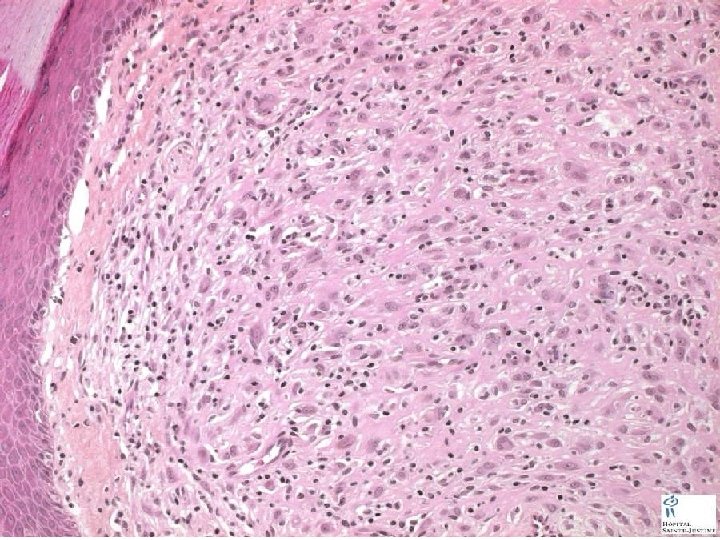

DERMIS TUMORS • DERMATOFIBROMA (BENIGN FIBROUS HISTIOCYTOMA) • DERMATOFIBROSARCOMA PROTUBERANS (DFP) • MALIGNANT FIBROUS HISTIOCYTOMA (MFH) • XANTHOMA • VASCULAR TUMORS of various types